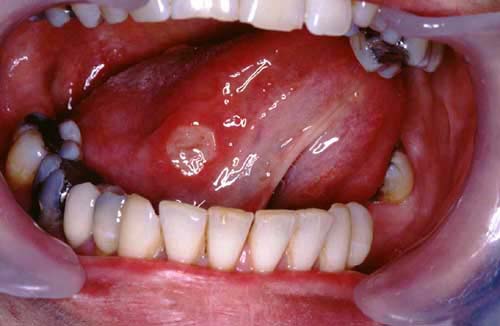

6. Bechet’s: Tongue aphthous ulcer